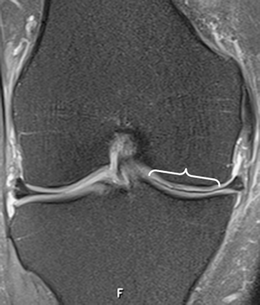

A total of 914 consecutive exams from 875 patients (524 men; mean age, 35 years) were reviewed. Vacuum phenomenon was found in 12 patients (prevalence 1.3%). In six (50%) patients, VP mimicked a meniscal tear, with four cases simulating a torn medial discoid meniscus. The VP signal was not easily differentiated from meniscal signal on most sequences in most cases (9/12). Gradient-recalled echo (GRE) localizer images proved most definitive, with 3D SPACE images the next most effective. Fast spin echo (FSE) images were only occasionally able to differentiate VP from meniscus.

Rarely recognized on MR, VP can mimic meniscal pathology, potentially leading to inappropriate surgery. Because differentiation of VP from the meniscus is challenging on FSE at 3 T, radiologists should become familiar with the appearance of VP and review GRE localizer or 3D images carefully to avoid misinterpretation.